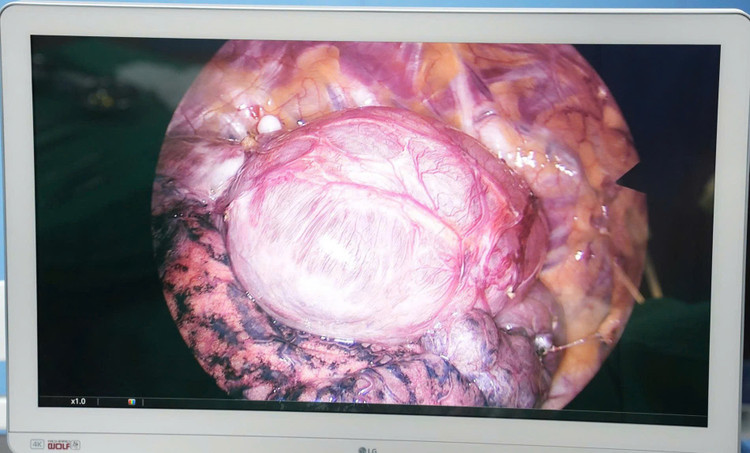

ken-phoi-2.jpg

Kén khí phổi khổng lồ - Ảnh BVCC